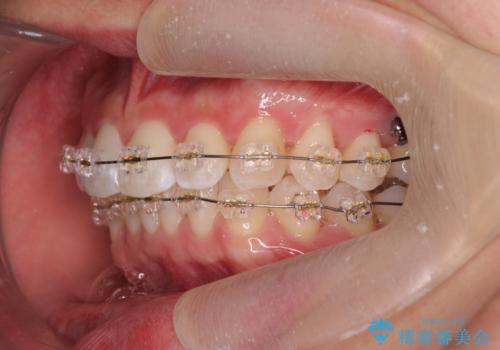

- 20代男性

- ワイヤー

- 10ヶ月

- 取り外しの必要なマウスピース矯正ではなくワイヤー矯正を希望され来院されました。

マウスピース矯正、ワイヤー矯正どちらの方法でも治療は可能ですが、ご要望の通りワイヤー矯正で歯の排列を行っていきます。